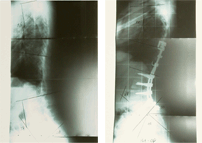

척추 후만증

척추 후만증 수술 전/후 X-ray

수술 전

수술 후